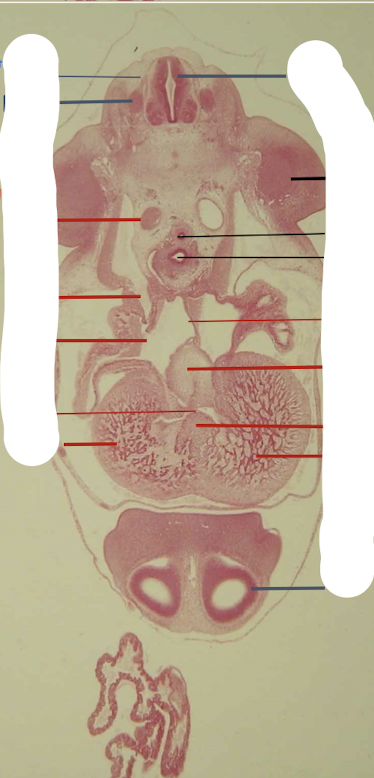

auditory ganglion (CN 8)

cerebral hemisphere

diencephalon

endolymphatic duct

geniculate ganglion

infundibulum

evagination of the prosencephalon → pituitary gland (ventral to Rathke’s pouch which becomes the pars distalis, pars intermedia, pars tuberalis of the pituitary gland)

jugular ganglion (CN 10)

Lens

Mesencephalon

(ventral to metencephalon)

Metencephalon

Myelencephalon

olfactory pits

otic vesicle

pigmented layer (retina)

rathke’s pouch

dorsal to infundibulum which is an evagination of the prosencephalon → pituitary gland (ventral to Rathke’s pouch which becomes the pars distalis, pars intermedia, pars tuberalis of the pituitary gland)

semilunar ganglion (CN5)

sensory layer (retina)

green is pigmented layer

spinal cord

superior ganglion (CN9)

Telencephalon

diencephalon → telencephalon → cerebral hemisphere